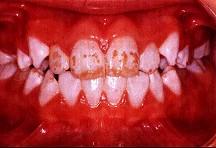

问题 关于氟斑牙的临床表现下列哪项不正确 ( )

选项 A.同一时期萌出的釉质上有黄白相间斑块 B.重者并有釉质缺损 C.多见于乳牙和恒牙 D.对酸蚀的抵抗力强 E.对摩擦的耐受性差

答案 C